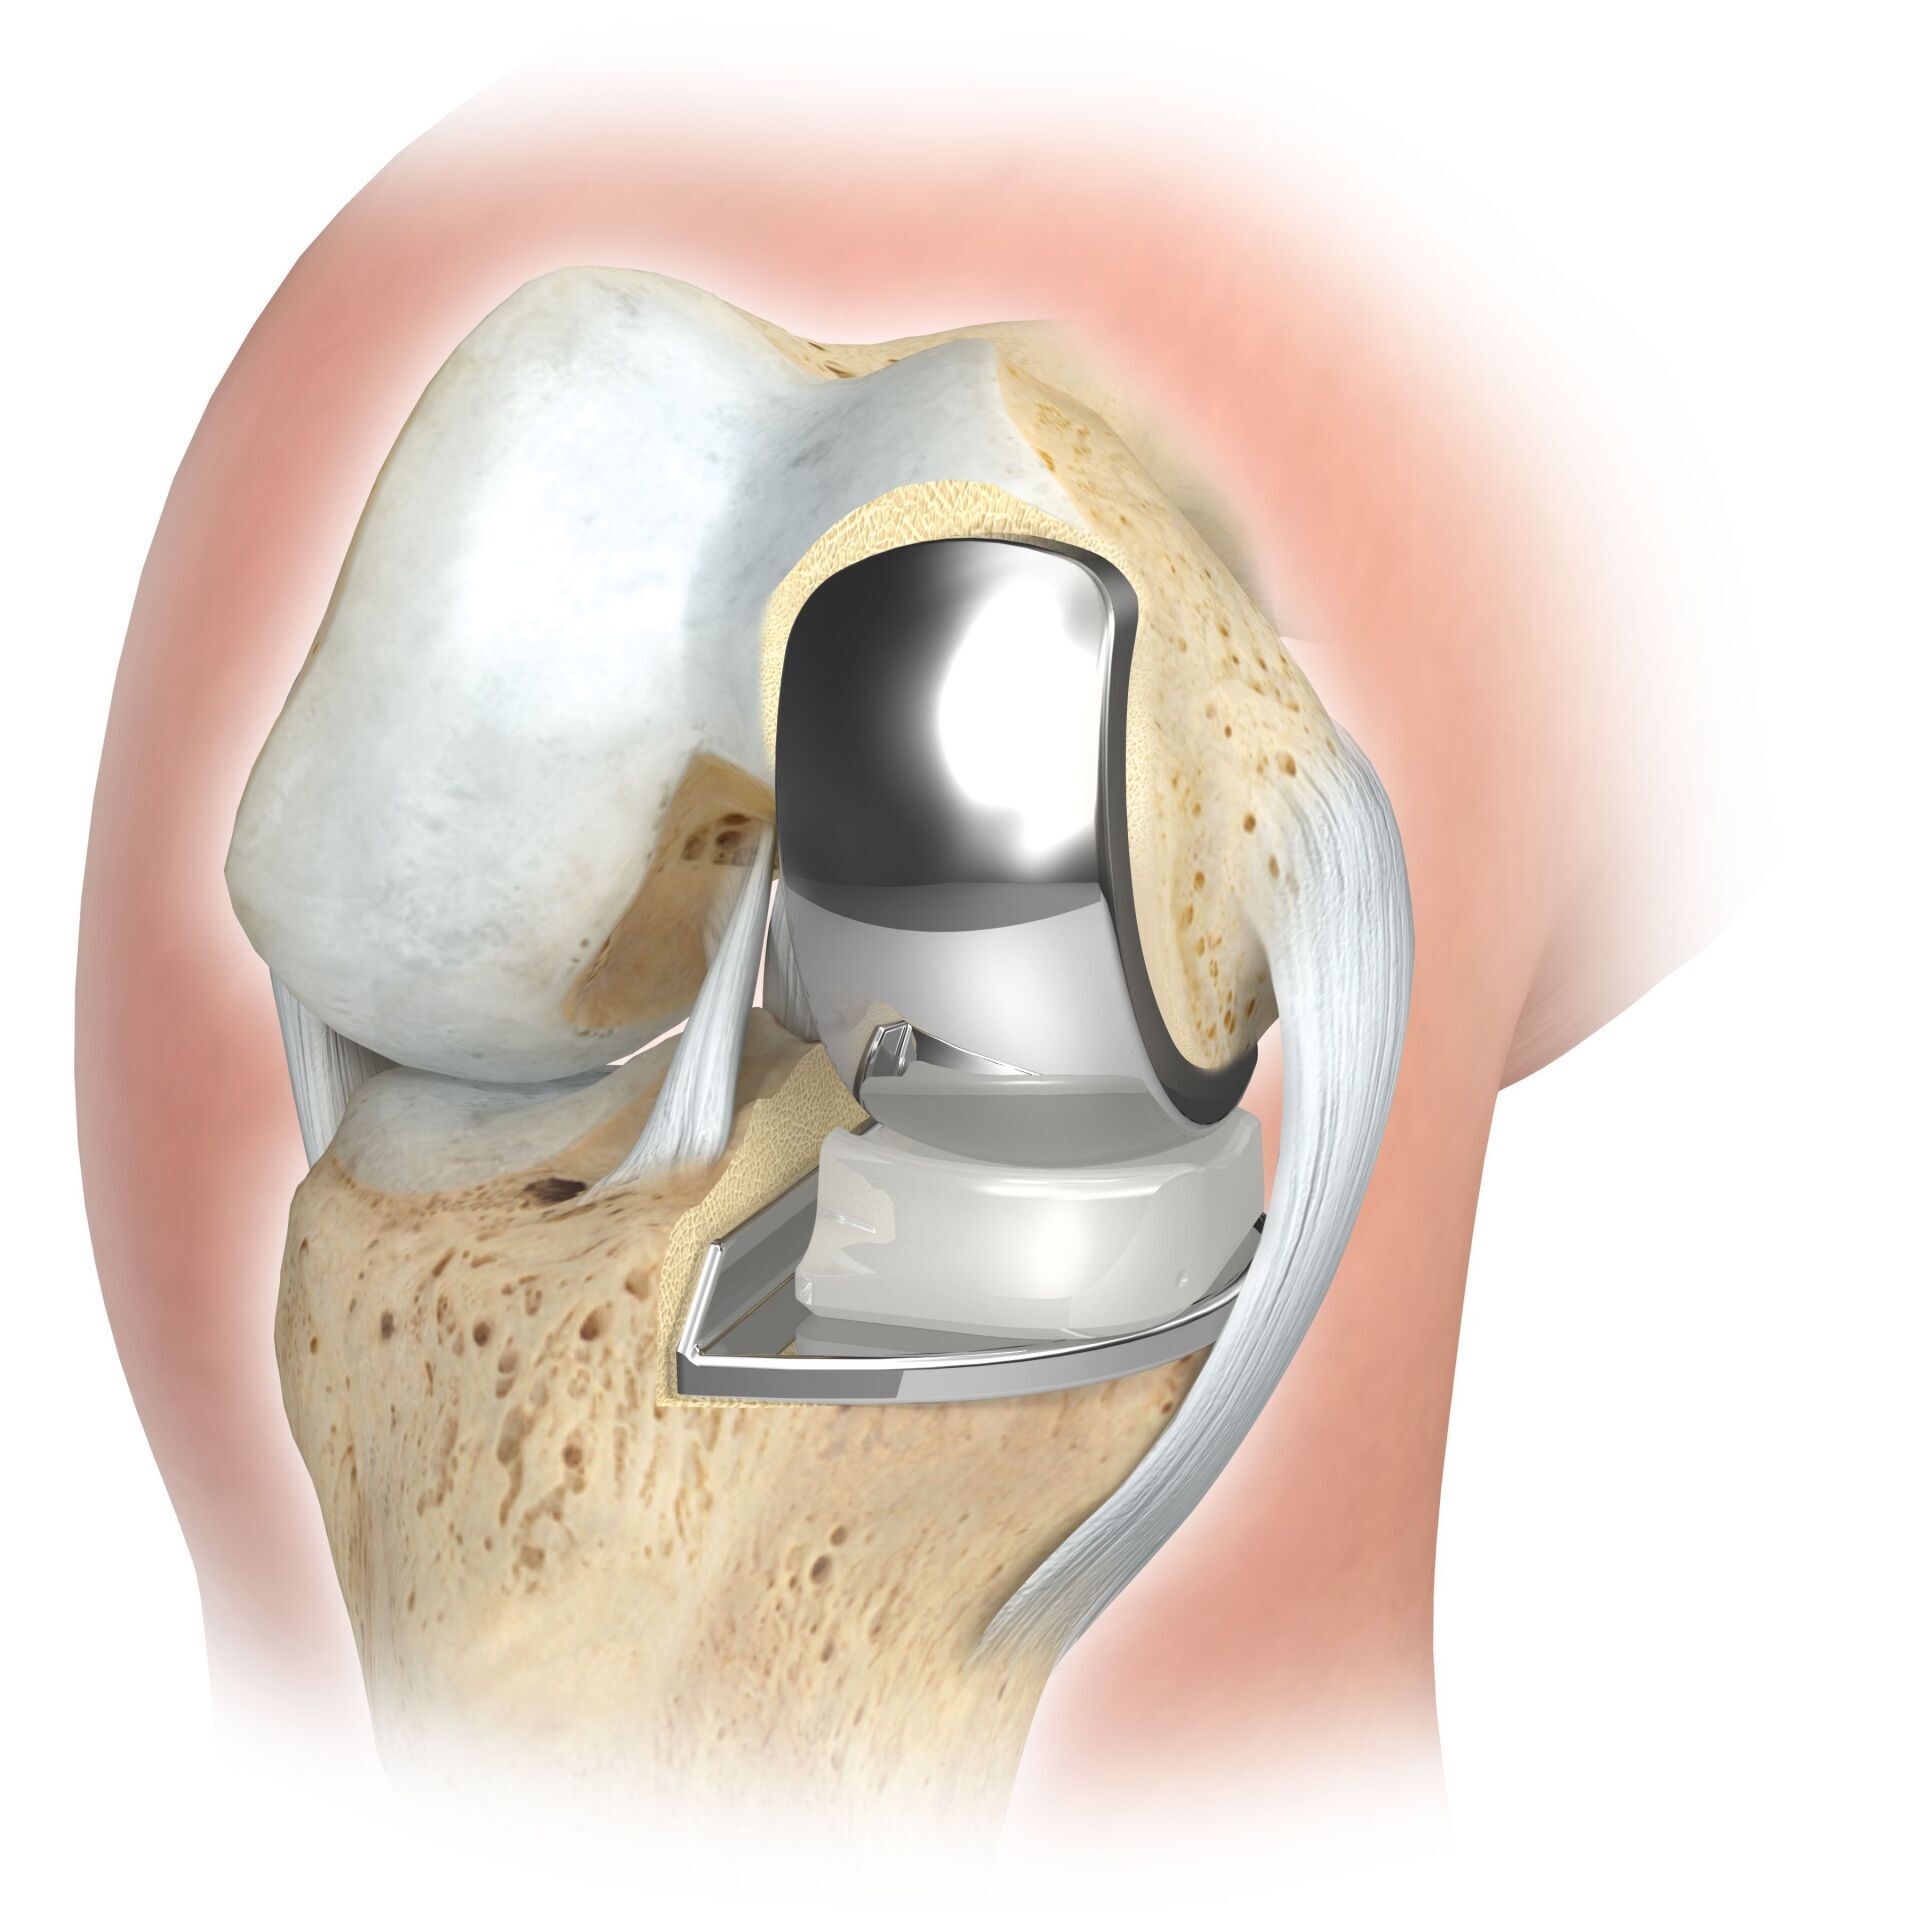

TKA (ARTIFICIAL KNEE JOINT)

The artificial knee joint replaces the cartilage surface that has been destroyed by osteoarthritis.

The underlying bone on the femur and tibial head remains intact. Some compare a modern artificial knee joint to a crowning of a tooth; the exact term is the so-called

bicondylar resurfacing. Between the new surfaces on the upper and lower leg is the so-called inlay made of a specially hardened white plastic, which can be seen in the X-ray image as the distance between the metal parts.